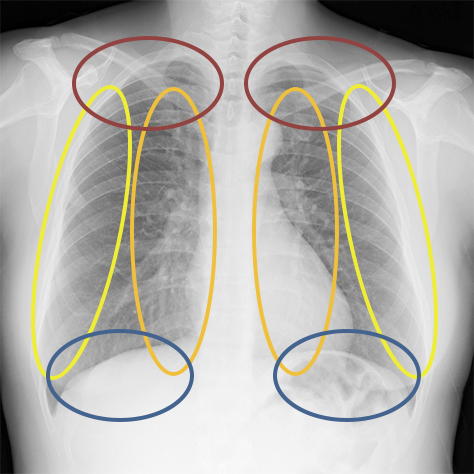

PLAMAX MF-72 minimum factory イングラム & クラブマン, Bone Suppression処理(胸部骨減弱処理) | コニカミノルタ,

Bone Suppression処理(胸部骨減弱処理) | コニカミノルタ, Bone Suppression処理(胸部骨減弱処理) | コニカミノルタ,

Bone Suppression処理(胸部骨減弱処理) | コニカミノルタ,S.H.MonsterArts ゴジラ(2016) 第4形態 夜間戦闘Ver.